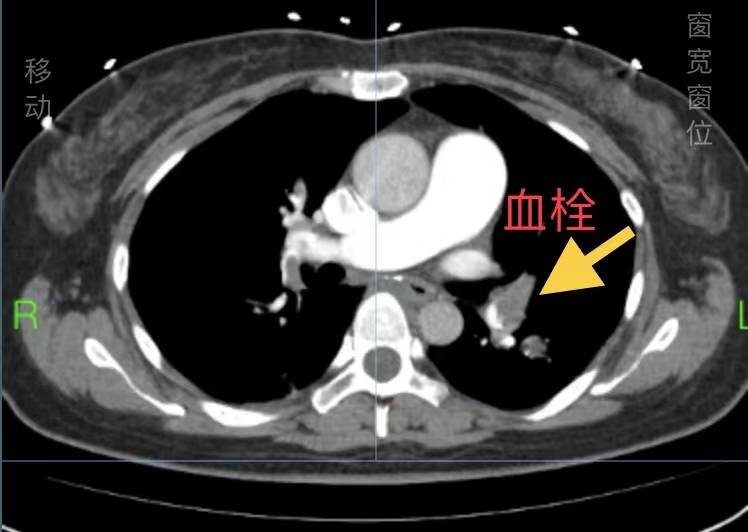

因刘女士新型冠状病毒感染,本着“应收尽收”原则,首诊收住感染二部。感染科二部胡滨主任及介入三科颜鹏主任嗅到了不一样的气息:患者虽然新型冠状病毒感染诊断明确,但患者出现晕厥及血氧饱和度下降,需高度警惕肺栓塞这个“沉默的杀手”。当即完善肺动脉CTA,果不其然,肺动脉CTA提示:左、右主肺动脉远端及双肺动脉分支可见多发充盈缺损。病情极其危重,刻不容缓。颜鹏主任当晚为患者急诊行介入治疗。术中血氧饱和度当即由80%转为98%。术后再进一步予以对症支持治疗,刘女士顺利脱离了危险期,转危为安。

“急性大面积肺栓塞病死率极高,急性期死亡率可达50%以上。如不能得到及时诊治,不少患者在发病后1小时内死亡,尤其急性致死性大面积肺栓塞造成呼吸心脏骤停的患者,病死率最高可达95%。因发病极其隐匿,被称为“沉默的杀手””,颜鹏科主任医师介绍到:“当前新型冠状病毒肺炎患者数量急剧上升,因症状不明显号称”沉默性缺氧”,可表现为气促、胸闷、低氧血症等表现。与肺动脉栓塞具有高度的相似性!如目光仅仅聚焦于新冠肺炎,可能忽视“沉默的杀手”,后果不堪设想!对于急性肺栓塞患者,如能尽早前往医院救治,可取得较为满意的疗效。”(介入血管三病区)